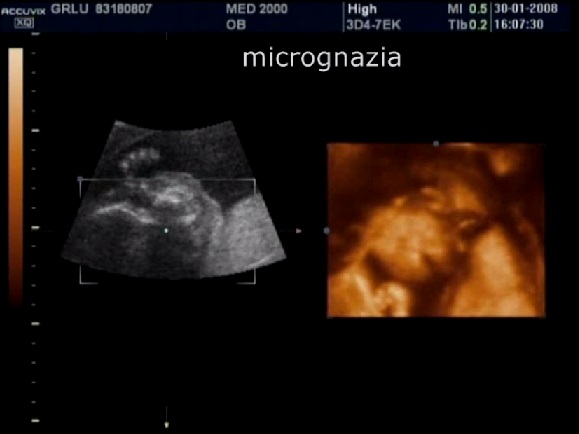

2. micro-retrognazia